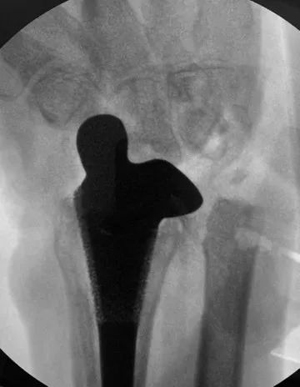

经过3个多小时的手术,小周受损的腕关节被全新的人工腕关节系统所代替,术中检查关节稳定性和活动度良好,影像学指标和预期的结果也基本一致。陈山林主任说:“小周的腕关节预期能获得50度屈伸活动,可以满足日常生活要求。”

患者手术前X光片 患者手术后x光片